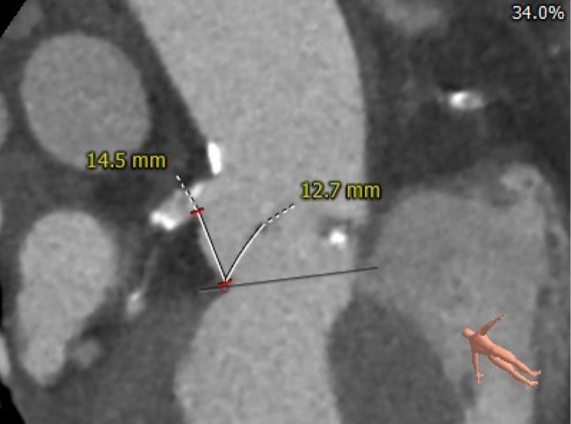

主动脉根部评估

CT 数据显示该患者为三叶式主动脉瓣